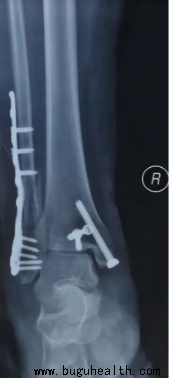

2.手术治疗

对于Ⅲ级踝关节扭伤及保守治疗无效者可以考虑手术治疗,具体方法有直接缝合、带线锚钉修复、伸肌支持带加强修复、肌腱移植重建等,对于骨折错位患者,也可以选择手术治疗。